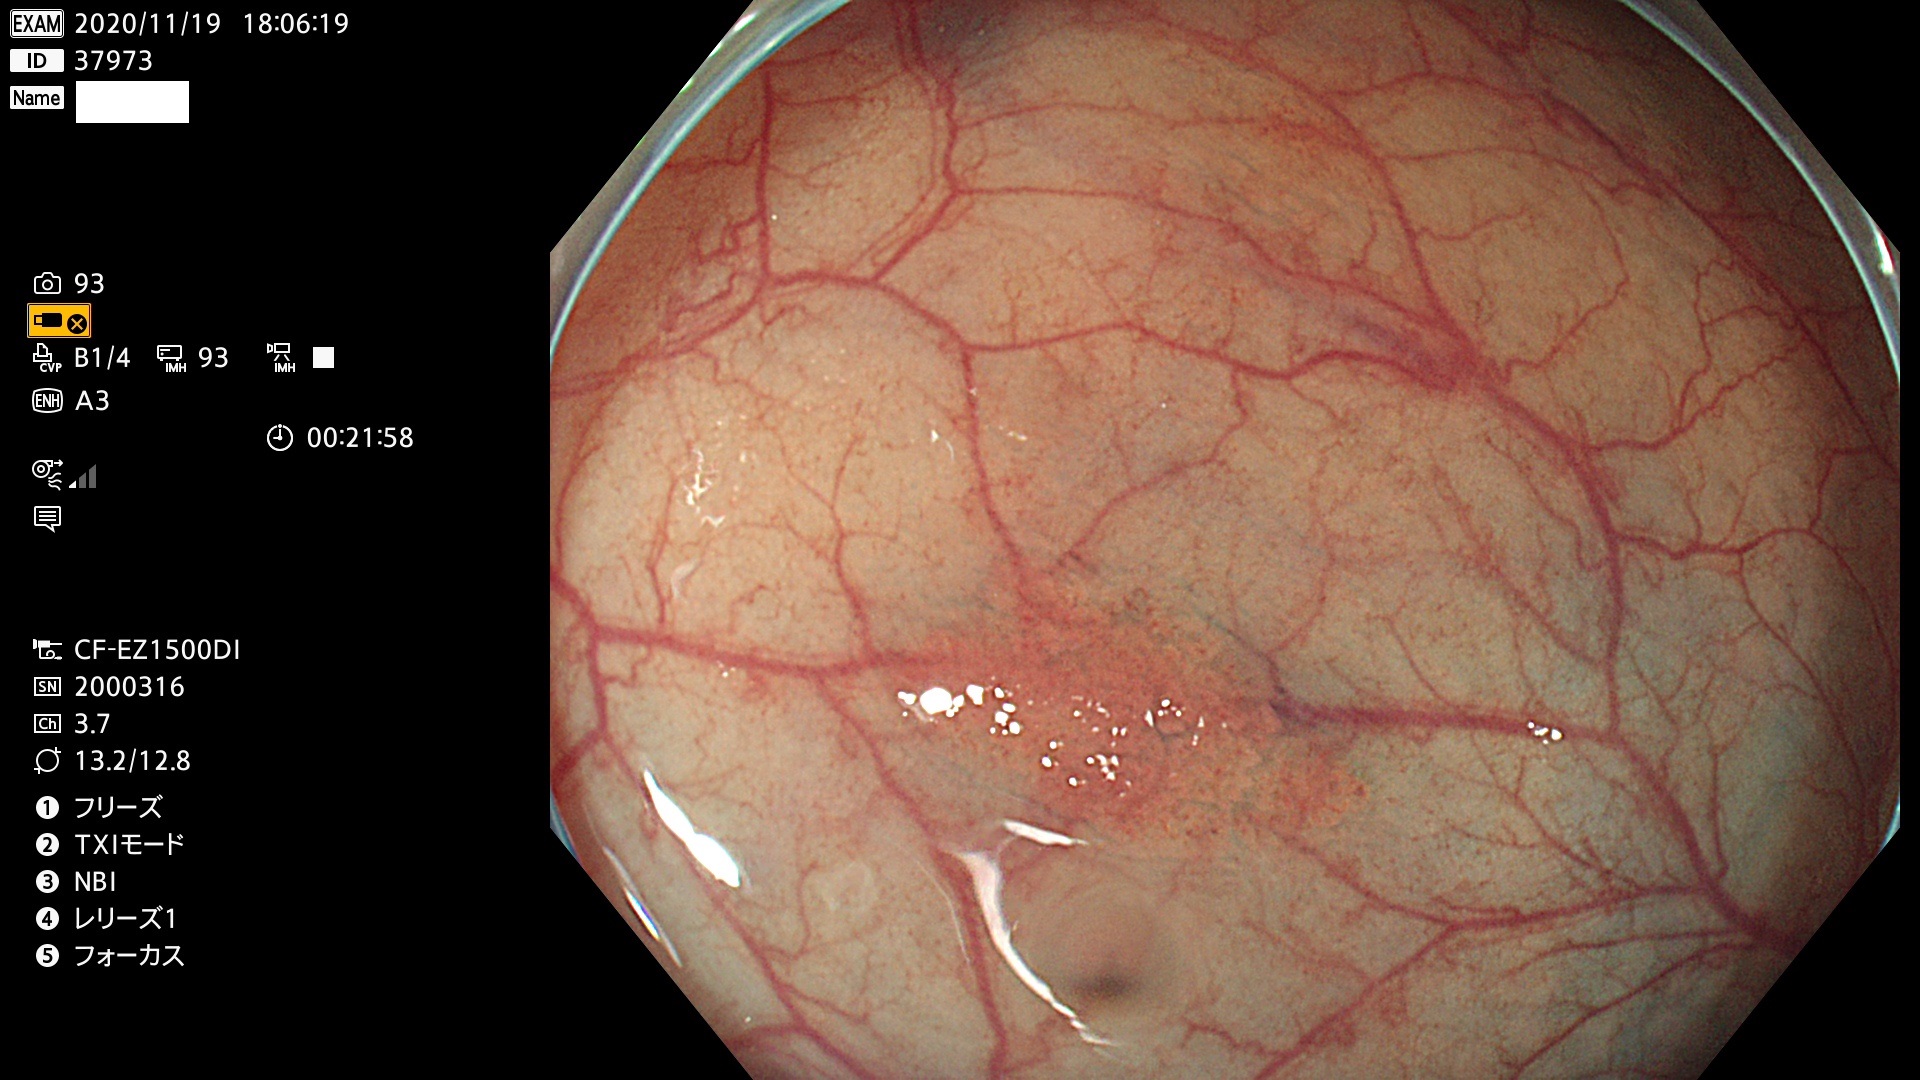

発見困難で危険性の高い平坦型病変(上記100名より抽出)

37900 37902 37903 37904 37905 37906 37907 37909 37910 37911 37912 37913 37914 37915 37916 37917 37919 37921 37922 37923 37926 37928 37929 37930 37931 37933 37934 37935 37936 37937 37938(SSAPのみ) 37939 37940 37941 37942 37943 37946 37947 37948 37949 37951 37952 37953(SSAPのみ) 37955 37956 37957(SSAPのみ) 37958(SSAPのみ) 37960 37962 37963 37964 37966 37967 37968 37971 37972 37973 37975 37976 37977 37979 37982 37983 37984 37985 37986 37987 37988 37989 37990 37991 37992 37993 37994 37995 37996 37998 37999